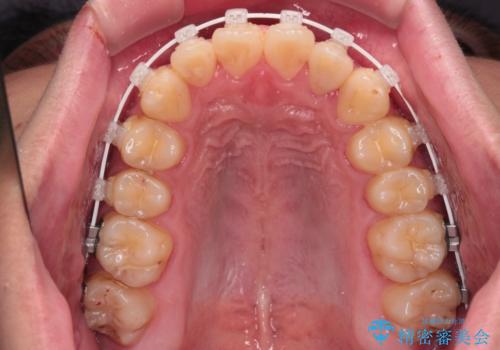

- 審美装置

一日中マウスピースを装着する煩わしさから、マウスピース矯正を継続する自信がないとのことで、ワイヤー装置にて矯正治療を行うこととしました。

気になっていたクロスバイトは速やかに改善され、1年間で治療を終えることができました。